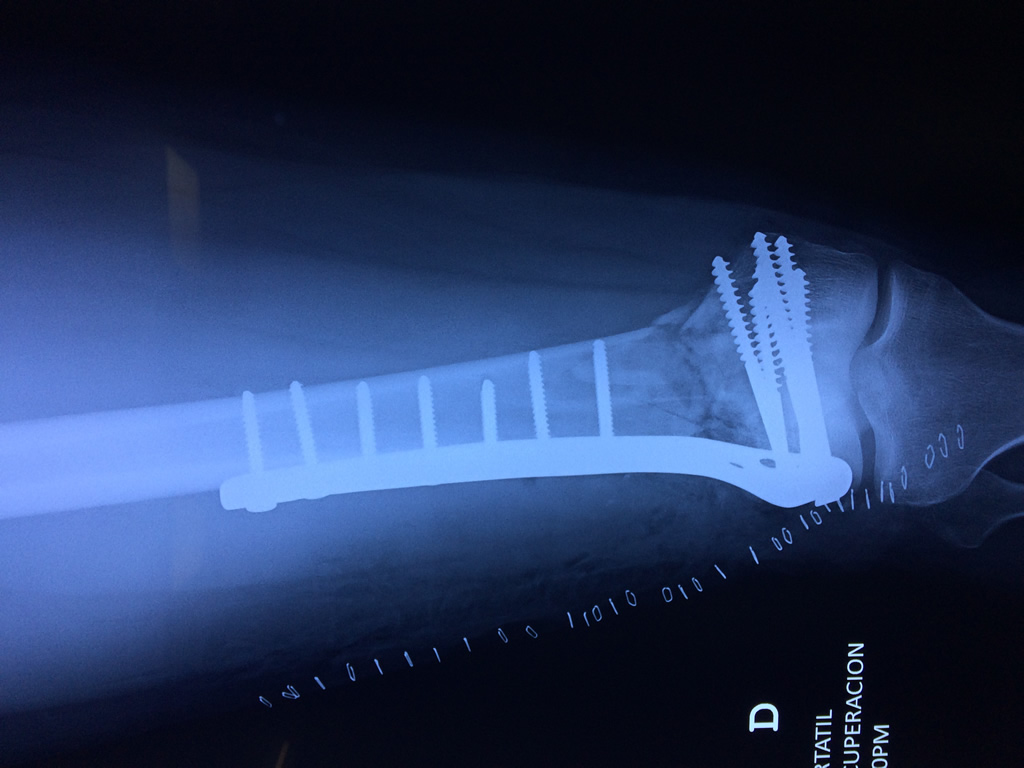

Cirugía de Tibia y Peroné